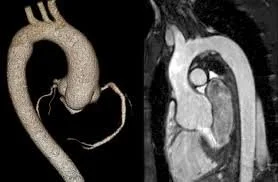

Overview of the Anatomy

The aorta is the body’s largest artery. It carries oxygen-rich blood from the heart to every organ and tissue. Starting at the heart, it travels upward, makes a curve, then descends through the chest and belly, giving off branches that supply blood to the brain, arms, legs, and vital organs.

The aorta is essential for life; healthy blood flow depends on its strength and shape. Problems with the aorta, like tears or bulges, can be very serious.